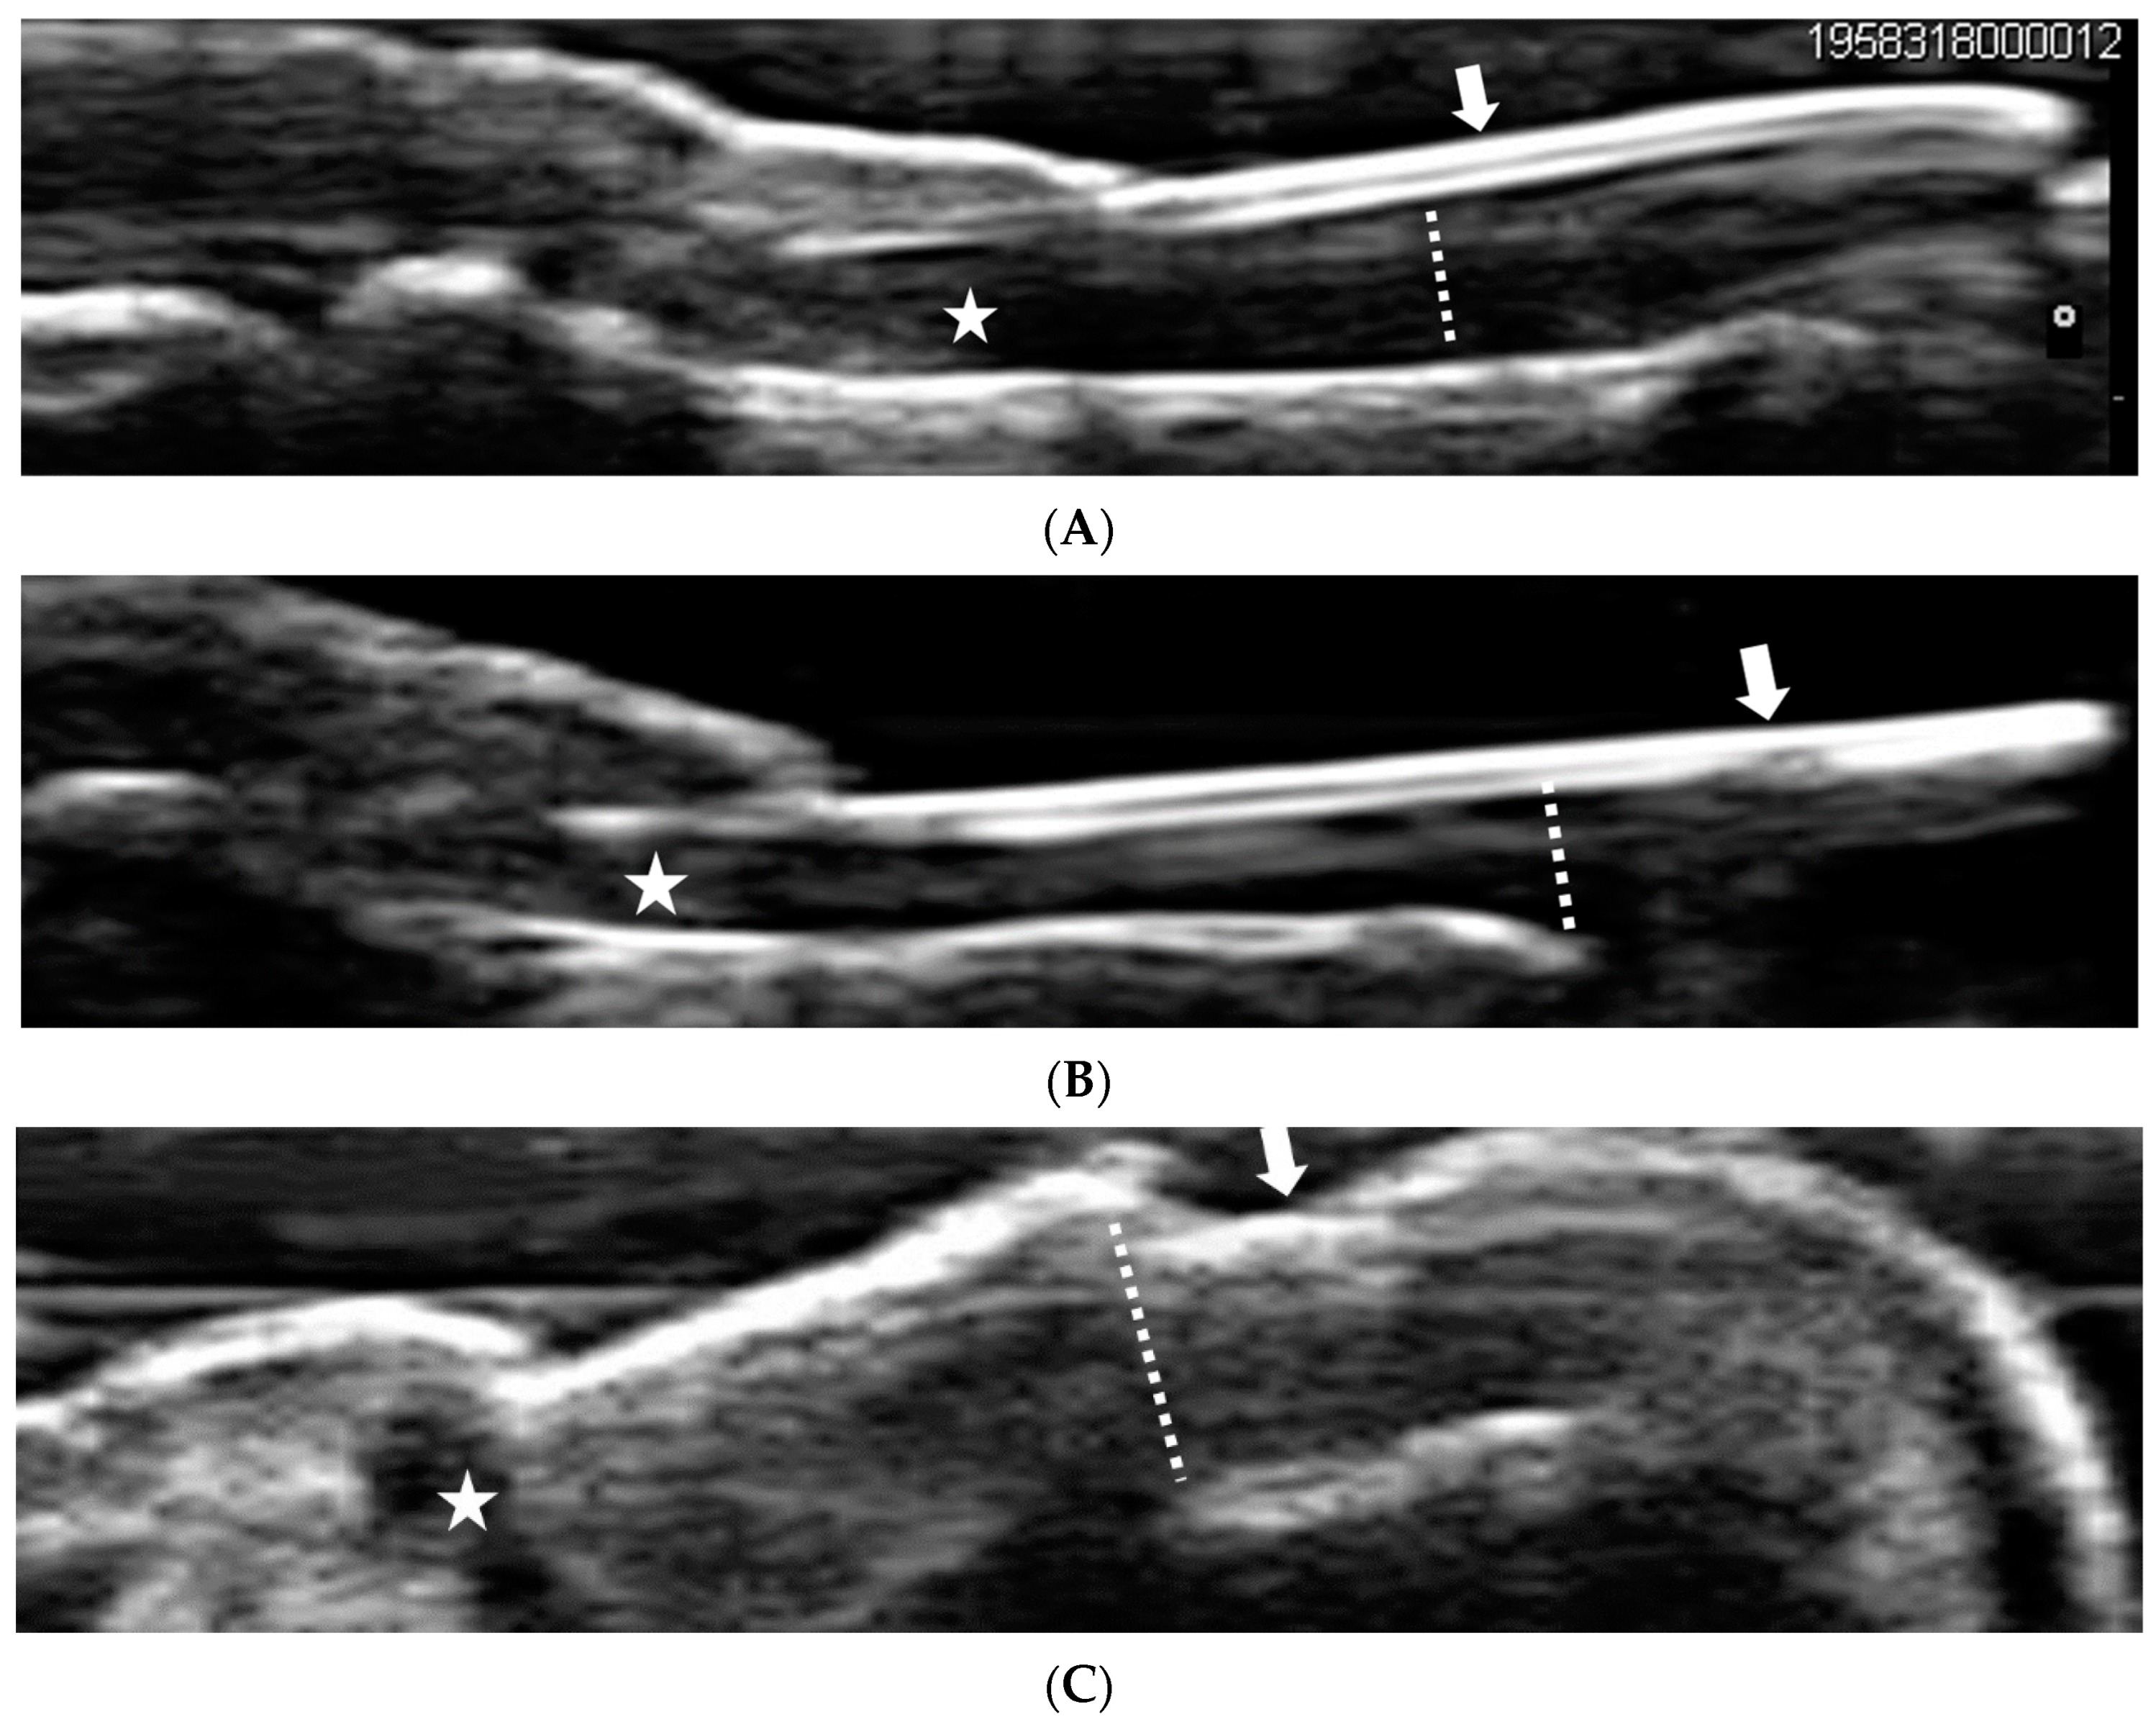

3.3. Ultrasonographic Findings at the Lower-Limb Enthesis